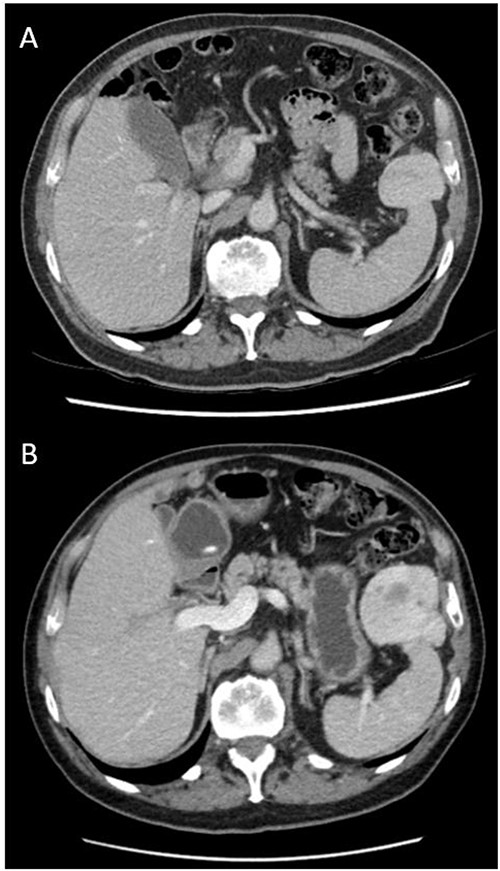

He was initially managed conservatively with surveillance imaging. Repeat CT abdomen pelvis 18 months after original imaging revealed an interval increase in the peri-splenic tumour (64 × 54 × 86 mm3), displaying a more prominent central area of decreased attenuation and peripheral cystic changes (Fig. 1). The lesion was abutting the anterior aspect of spleen and adjacent diaphragm. No abdominal lymphadenopathy was noted. Gastroscopy and colonoscopy were performed, confirming an extraluminal lesion. Due to continued diagnostic uncertainty, diagnostic laparotomy and excisional biopsy was performed.

Axial views and comparison of original CT abdomen pelvis to 18-months later. (A) Contrast-enhanced CT abdomen pelvis (arterial phase): axial slice showing solid mass laterally in the left upper quadrant adjacent to the spleen measuring 49 × 39 mm2. The spleen is otherwise normal (B) Contrast-enhanced CT abdomen pelvis 18-months after original (arterial phase): Axial slice showing larger mass measuring 64 × 54 × 86 mm3 with persistent heterogeneous enhancement and prominent central area of decreased attenuation and peripheral cystic changes.